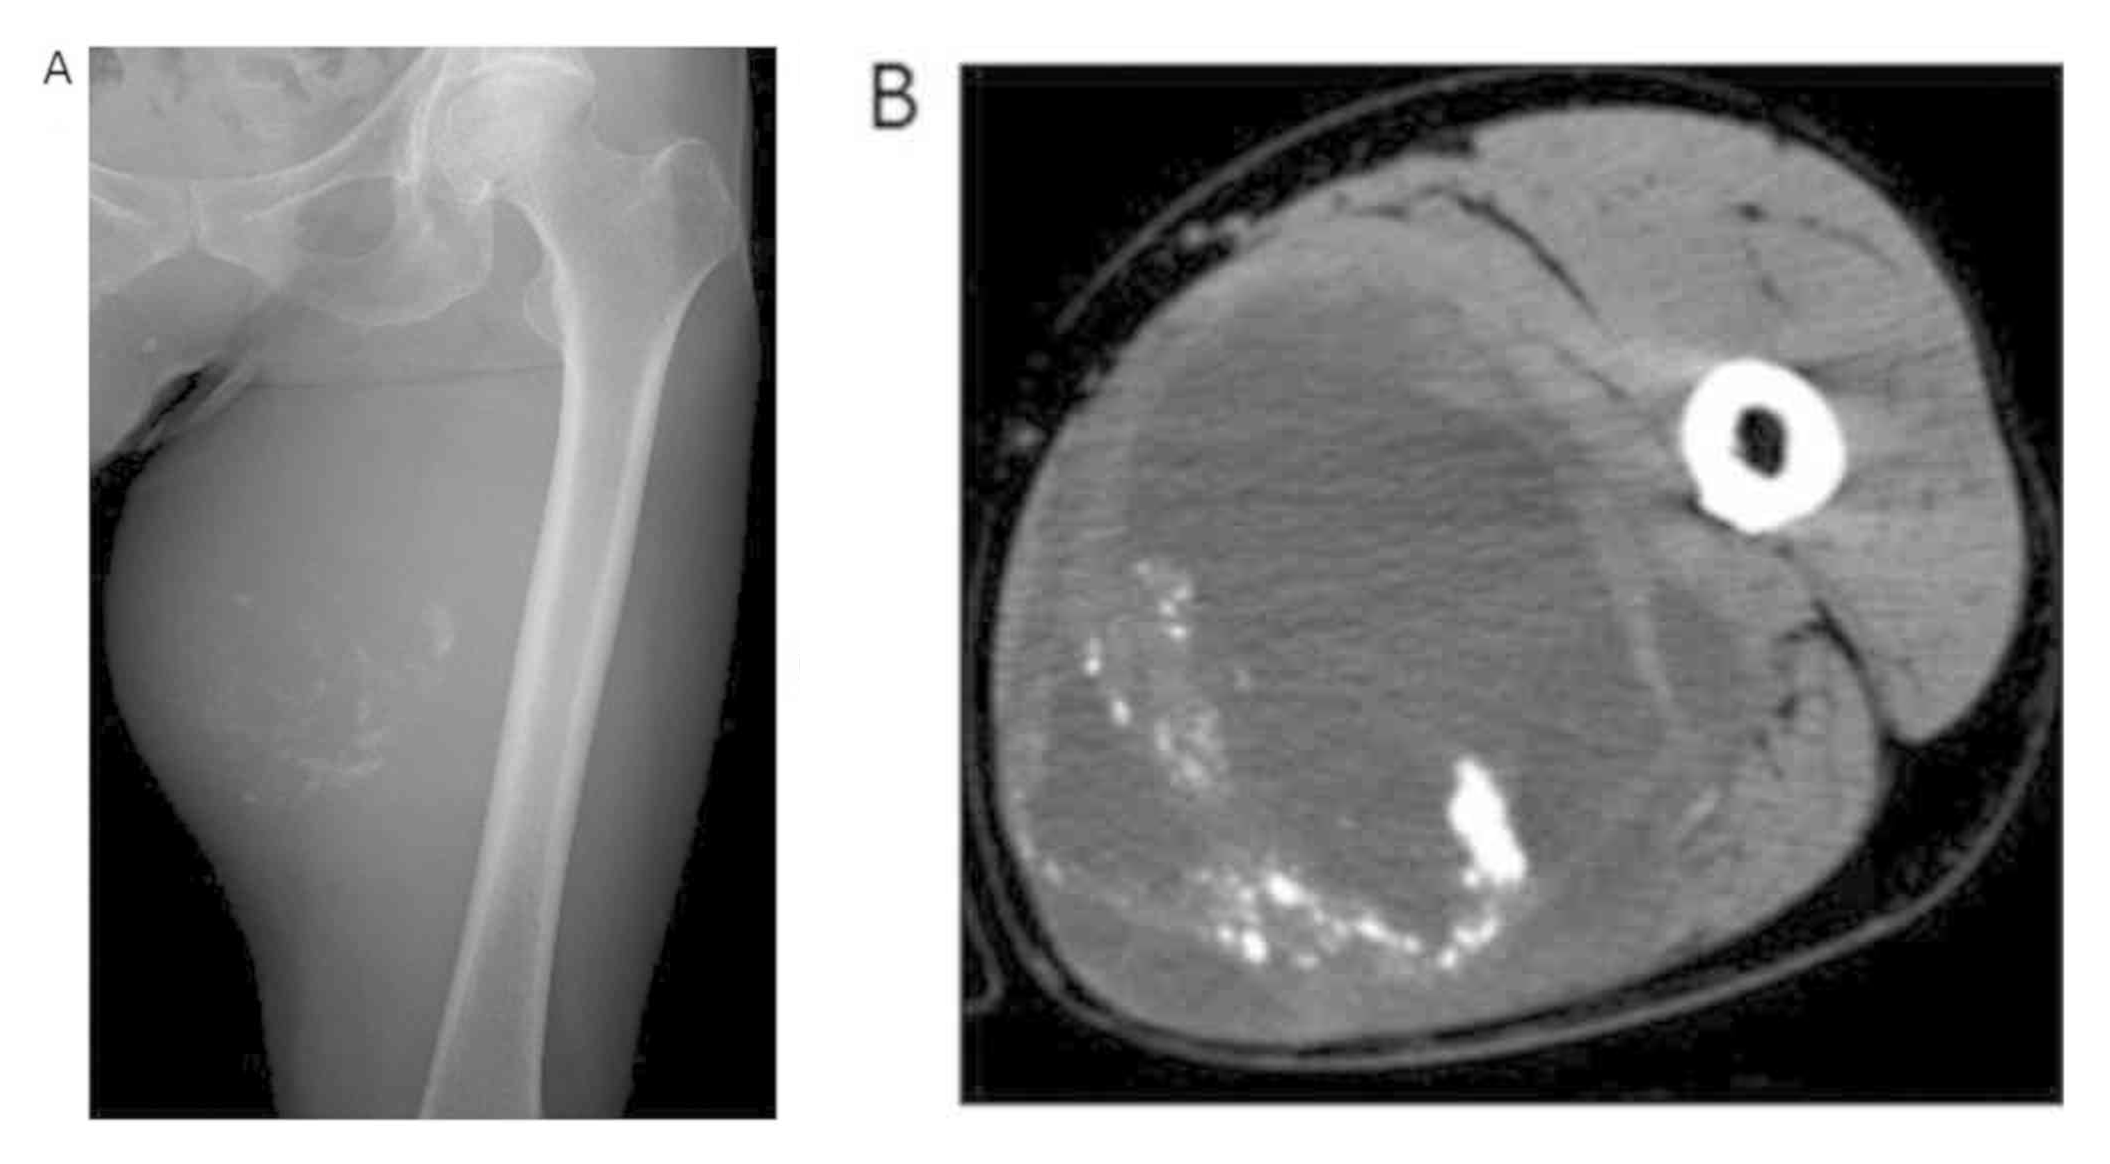

3.1 Radiografía simple

- 💡 Masa de partes blandas con calcificaciones u osificaciones amorfas, irregulares y desorganizadas, localizadas predominantemente en el centro de la lesión.

- 💡 Patrón en "nubes" o "algodonoso", similar a la matriz osteoide del osteosarcoma óseo.

- 💡 No hay unión a la cortical ósea adyacente (puede haber erosión por compresión, pero no infiltración directa).

- 💡 Puede ser visible una pseudocápsula radiolúcida que separa la masa del hueso.

3.2 Tomografía computarizada (TC)

- 💡 Masa de densidad heterogénea, con áreas de alta atenuación correspondientes a la matriz osteoide calcificada.

- 💡 Demuestra con precisión la falta de continuidad con el esqueleto, criterio esencial para el diagnóstico.

- 💡 Puede mostrar áreas de necrosis hipodensas y realce periférico tras contraste.

- 💡 Útil para planificación quirúrgica y para detectar metástasis (TC torácico obligatorio).

Hallazgo radiológico característico